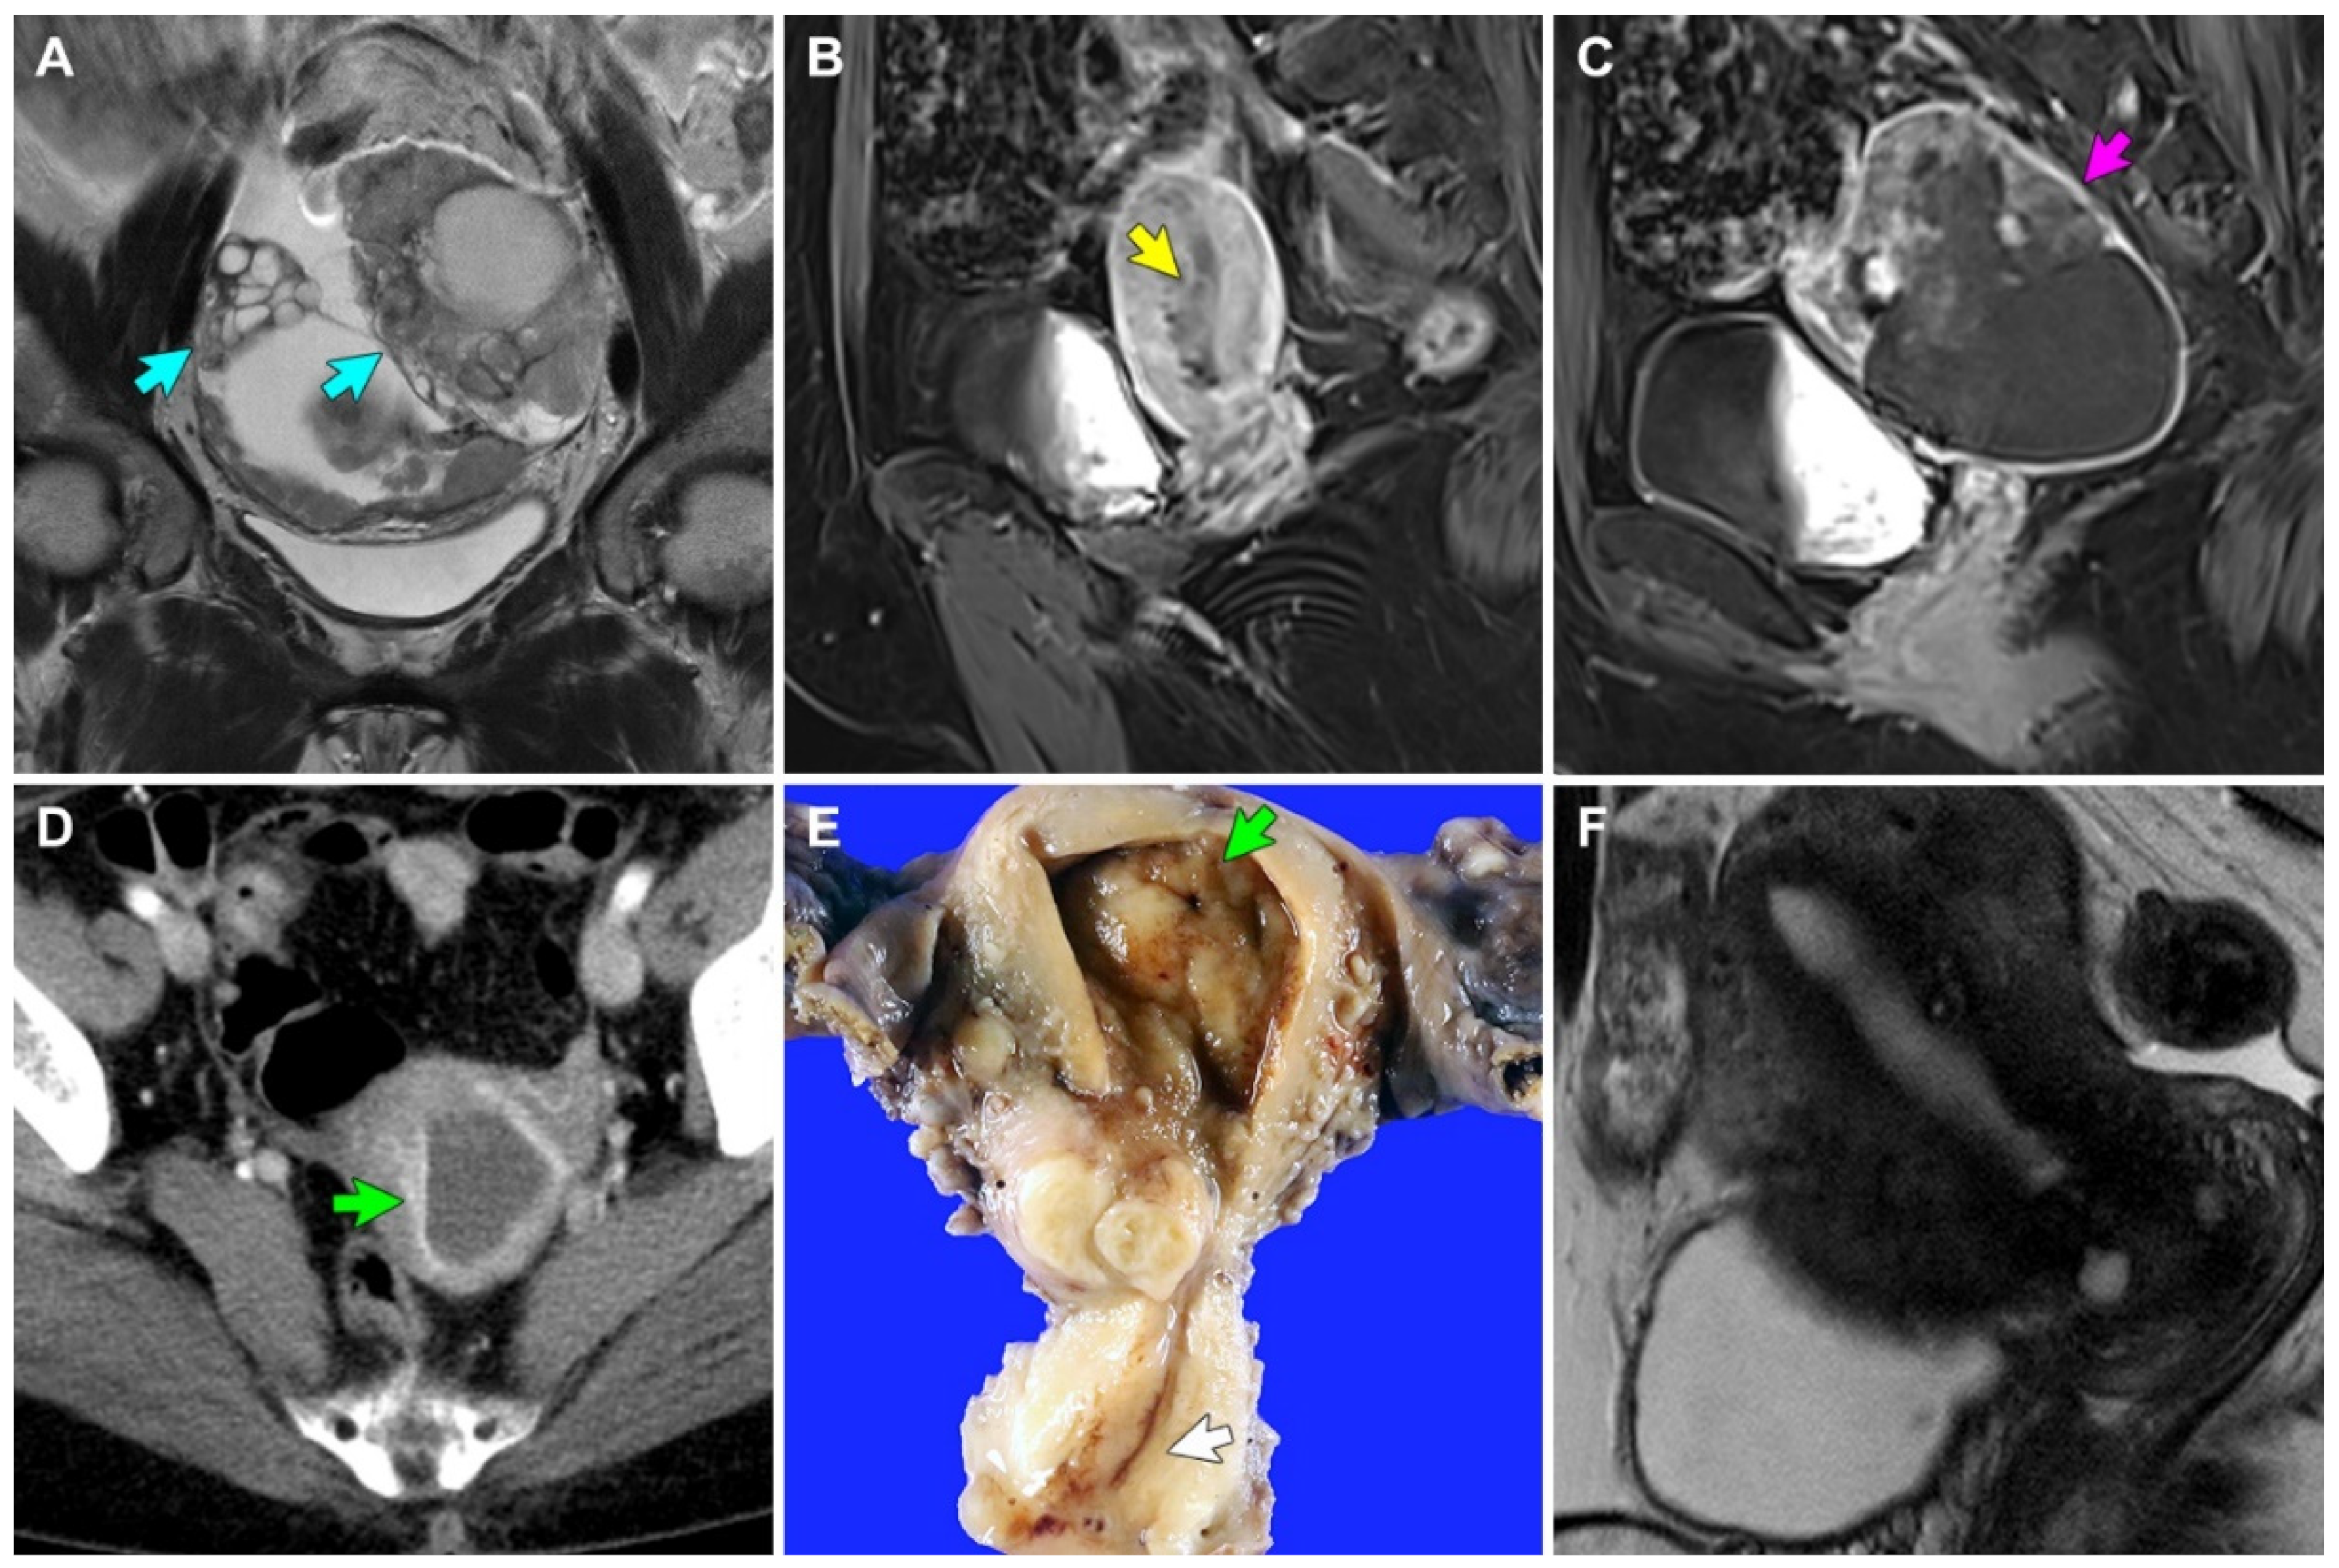

Figure 1.

MRI, CT, and gross findings. (A) Case 1: T2-weighted coronal MR image reveals solid and cystic bilateral ovarian masses (blue arrows). (B,C) Case 2: T1-weighted Dixon sagittal MR images reveal (B) 3.4 cm endometrial mass (yellow arrow) and (C) 8.6 cm solid and cystic left ovarian mass (purple arrow). (D) Case 3: Contrast-enhanced CT image reveals a 1 cm endometrial mass (green arrow) and hematometra. (E) Case 3: An irregularly elevated mass is noted in the endometrium. The endometrial cavity is distended with blood. The endocervix (white arrow) appears unremarkable. (F) Case 4: T2-weighted sagittal MR image reveals no identifiable lesion in the endometrium.

Case 1: A 33-year-old woman with polycystic ovary syndrome was referred to our institution for the evaluation and management of adnexal masses, after visiting an outside hospital with lower abdominal discomfort. Abdominopelvic computed tomography (CT) and magnetic resonance imaging (MRI) revealed an 8.6 cm solid and cystic left ovarian mass and a 4.0 cm solid right ovarian mass (Figure 1A). An omental cake was noted, and some metastatic nodules were also identified in the cul-de-sac and right round ligament. Additionally, the retroperitoneal lymph nodes were mildly enlarged, and the endometrium was unremarkable. Following three cycles of neoadjuvant chemotherapy with paclitaxel and carboplatin, the patient underwent interval debulking surgery, including a total hysterectomy with bilateral salpingo-oophorectomy, pelvic and para-aortic lymph node dissection, omentectomy, peritoneal mass excision, and low anterior resection. The final pathological diagnosis was grade 3 EC of the bilateral ovaries, involving the omentum, rectosigmoid colon, and peritoneum (FIGO stage IIIC). We also identified a 2.4 cm polypoid mass originating from the upper endocervix, with histological examination revealing several areas of EC that spread along the surface and invaded the polyp stroma. She received three cycles of post-operative adjuvant chemotherapy with paclitaxel and carboplatin. However, she presented with chest wall pain 49 months postoperatively, and chest CT and thoracic wall MRI revealed a 2.8 cm metastatic mass involving the upper sternal body and right parasternal area. She underwent complete surgical excision. Pathological examination of the mass confirmed the metastasis of ovarian EC to the sternum and rib. She is currently alive without evidence of recurrent disease, 67 months postoperatively.

Case 2: A 57-year-old woman was referred to our institution for the evaluation and management of uterine and adnexal masses, after visiting an outside hospital with lower abdominal pain and undergoing abdominopelvic CT and MRI. She had a history of hypertension, diabetes mellitus, pulmonary tuberculosis, and hypothyroidism. Imaging revealed a 3.4 cm endometrial mass with soft tissue density (Figure 1B) and an 8.6 cm solid and cystic left ovarian mass (Figure 1C). The retroperitoneal lymph nodes were enlarged, but pelvic and iliac chain lymph nodes were unremarkable. Peritoneal seeding or hematogenous metastasis were not observed. Radiological differential diagnoses included concurrent endometrial and ovarian carcinomas or endometrial carcinoma with ovarian metastasis. The endometrial curettage was diagnosed as grade 1 EC. Total hysterectomy with bilateral salpingo-oophorectomy, pelvic lymph node dissection, pelvic peritonectomy, appendectomy, and a small bowel resection were performed. Several enlarged mesenteric lymph nodes were detected intraoperatively but could not be completely resected. The final pathological diagnosis was synchronous endometrial grade 1 EC involving more than half of the myometrium (FIGO stage IB) and ovarian grade 3 EC involving the abdominopelvic peritoneum and small bowel (FIGO stage IIIC). We also identified a 2 cm ECP originating from the upper endocervix and showing a single microscopic focus of EC, involving the surface and superficial stroma of the polyp. Follow-up CT after three cycles of post-operative adjuvant chemotherapy with paclitaxel and carboplatin revealed a newly developed 5 cm necrotic mass invading the small bowel. She was switched from chemotherapy to pembrolizumab following metastatic recurrence and is currently alive with disease, three months postoperatively.

Case 3: A 57-year-old woman was referred to our institution for the evaluation and management of an incidentally detected endocervical mass. She underwent endocervical curettage at an outside hospital and was diagnosed with grade 1 EC involving ECP. Abdominopelvic CT revealed a 1 cm endometrial mass that appeared to be invading the superficial myometrium (Figure 1D). Cervical stenosis and hematometra were noted. However, no evidence of peritoneal seeding, lymph node enlargement, or distant metastasis was noted. A total hysterectomy with bilateral salpingo-oophorectomy and pelvic lymph node dissection was performed, and the specimen revealed several foci of grade 1 EC, measuring up to 0.8 cm (Figure 1E). The tumors were confined within the endometrium (FIGO stage IA). She received no further adjuvant treatment and is currently alive without evidence of recurrent disease, 24 months postoperatively.

Case 4: A 52-year-old woman without previous gynecological history received an endocervical polypectomy at an outside hospital and was referred to our institution for further evaluation and management. The polypectomy specimen was determined to be a grade 1 EC involving ECP. Abdominopelvic MRI revealed no visible neoplastic lesions in the cervix, endometrium, lymph node, and abdominopelvic peritoneum (Figure 1F). Under the clinical impression of MRI-invisible endometrial cancer, total hysterectomy with bilateral salpingo-oophorectomy was performed. The final pathological diagnosis was grade 1 EC limited to the endometrium (FIGO stage IA). She received no further adjuvant treatment and is currently alive without evidence of recurrent disease 15 months postoperatively.